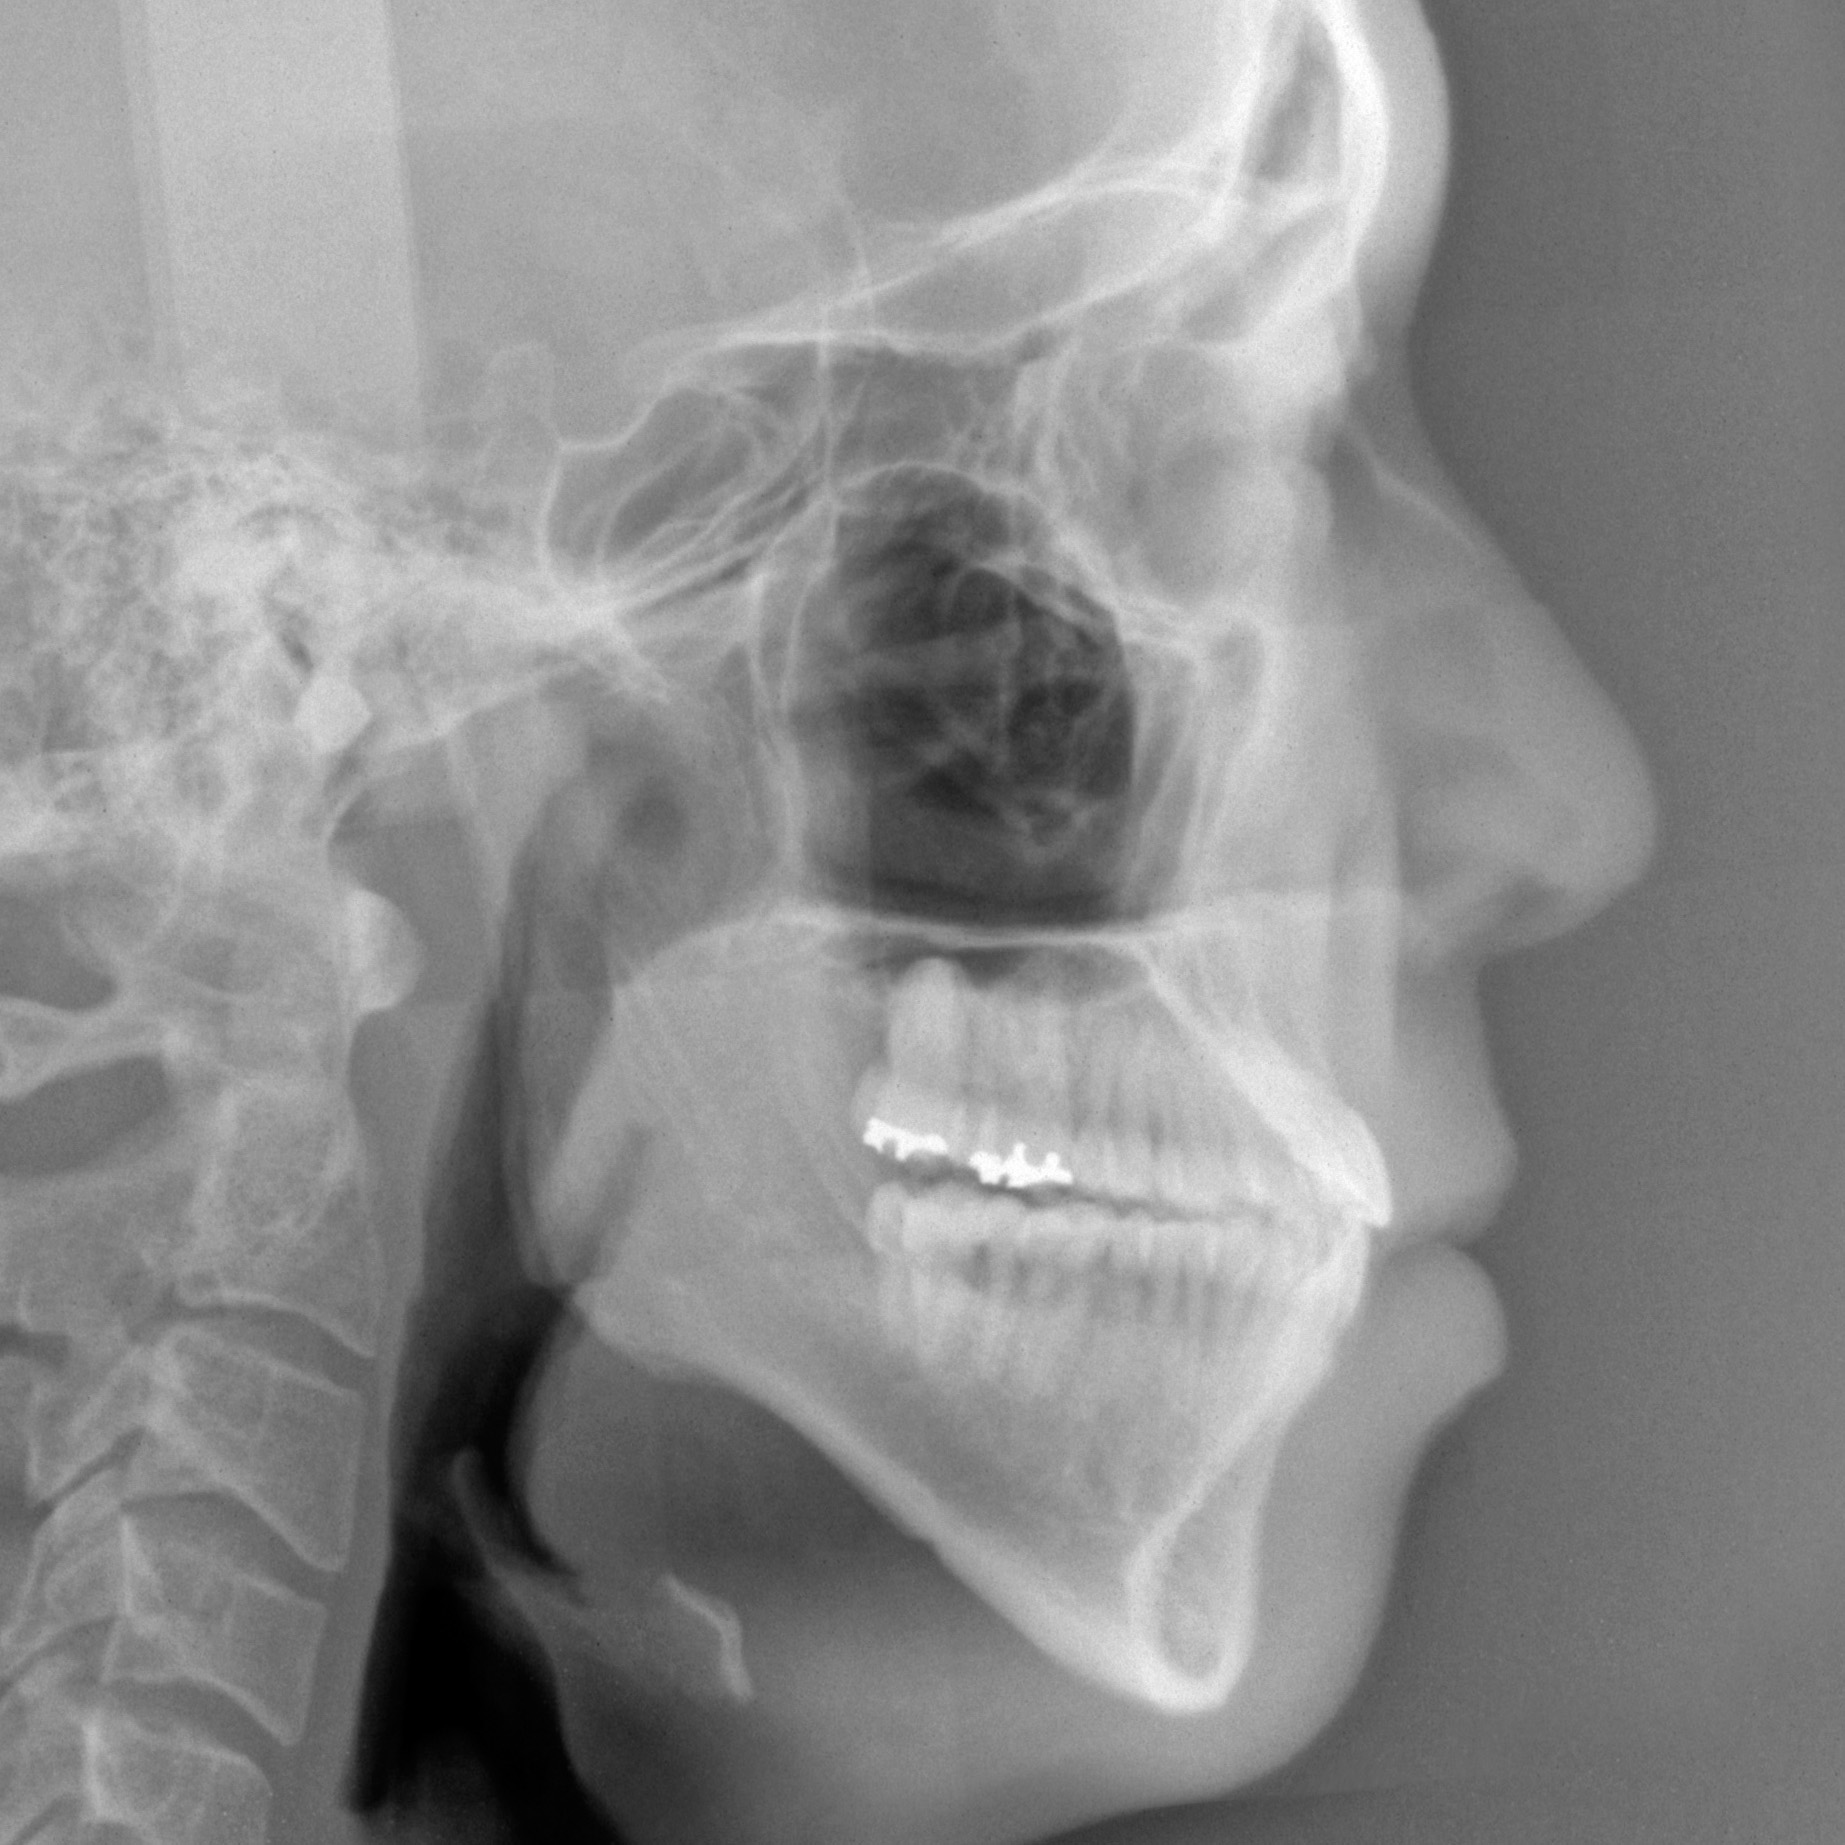

新着情報 150 治療後セファロ側面 Tweet 投稿日 : 2026年01月06日(火)カテゴリー : コメントを残す コメントをキャンセルメールアドレスが公開されることはありません。 * が付いている欄は必須項目ですコメント 名前 * メール * サイト 26歳 男性 「手術なしで 受け口を 治してほしい」(骨格的な要因を伴う 反対咬合) ≫